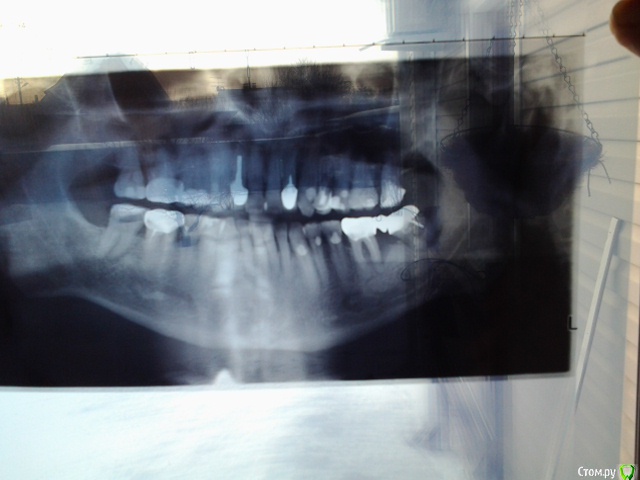

Евгения 66 Опубликовано 20 января, 2015 Автор Поделиться Опубликовано 20 января, 2015 (изменено) Справедливое замечание администратора принимаю :-)Сегодня сделала снимки повторно в другой клинике,правда,в электронном виде получить не удалось,только на рентгеновской плёнке. Сфотографировала,как смогла ( муж держал перед лампой,а я снимала :-). Но даже сама увидела как бы " брызги " цемента ниже корневых каналов. По ощущениям:если зубы не трогать,не болят,но если сверху совсем слегка постучать,больно,и боль потом " висит " ещё пару минут. 33-43 более чувствительны,чем 32. Чувствителен также старый "пенёк" 45,который был запломбирован ещё в 92 г.и стоял под старым снятым 12.01.м/к мостом. Каналы 32-43 пломбировали 09.01.,то есть 12 дней назад. 44 удалён 12.01. Вопрос:может ли попадание цемента в кость за пределы корневого канала быть причиной боли при постукивании или это нормальное следствие пломбировки канала? Может ли боль отдаваться от лунки удалённого 9 дней назад 44 зуба?И ещё большая просьба взглянуть на корень и канал 45 в плане его жизнеспособности и необходимости перепломбировки канала. Большое спасибо и простите за бестолковый пост от 17.01. Снимки прилагаю. Изменено 20 января, 2015 пользователем Евгения 66 1 1 Ссылка на комментарий

Евгения 66 Опубликовано 25 января, 2015 Автор Поделиться Опубликовано 25 января, 2015 Пытаюсь разобраться с зубами супруга. Стало не до своих:-). Попробую приложить 3 файла:1. ОРТОПАНТОМОГРАММА,с которой мы пришли в клинику ( частную ) в первый визит-09.01.с.г. Она сделана в другой клинике в феврале 14 г.,но никакого лечения мы там не начинали.2.ЗАПИСЬ В КАРТЕ О СОСТОЯНИИ ЗУБОВ на момент первого визита 09.01. За прошедшее после этого время произведены следующие работы: 15 зуб-пломбировка каналов+временная пломба; 36 и 38 зубы-удаление;47зуб-пломбировка каналов+временная пломба ( почему и здесь временная,мы также не поняли).3.ФОТОГРАФИИ ЗУБОВ ВЧи НЧ . Сделала сегодня,но снять дальние зубы и сделать фото с лингвальной стороны не получилось. Если передать столько файлов не получится,попробую переслать отдельными постами. Очень большая просьба дать Вашу оценку,что надо делать и чего НЕ НАДО. Очень пугает огромная программа,назначенная клиникой. И не столько из-за денег,сколько боимся излишнего вмешательства в зубы,которые,возможно,пока не надо трогать.В ПЛАНЕ ЛЕЧЕНИЯ :-8 КАРИЕСОВ,а я читала,что далеко не все кариесы надо трогать,то есть рассверливать.-8 ПЕРИОДОНТИТОВ ( 17,26,46,47,14,15,25,22) и 1 ПУЛЬПИТ(23) Как я понимаю,во всех этих зубах будет,как и в 15 и 47,пломбировка или перепломбировка каналов.-4 УДАЛЕНИЯ (уже сделанные 36 и 38,и ещё предстоящие-24 и 27 ) Удаления пугают больше всего. Может быть,эти зубы можно ещё спасти?7-6 ВКЛАДОК КХС и 8 м/к коронок,которые мы пока не понимаем где:-)-1 имплант через 4 мес.после лечения,но тоже не написано где. Если всё это,действительно,необходимо,мы пройдём этот путь. Но всё же очень хотелось бы узнать Ваше мнение,дорогие и многоуважаемые доктора! За Ваш любезный ответ заранее очень благодарны! Ссылка на комментарий

Евгения 66 Опубликовано 25 января, 2015 Автор Поделиться Опубликовано 25 января, 2015 Возвращаюсь к своему вопросу от 17 января. Речь идёт о пломбировке каналов 32-43 зубов. Сначала у меня не было снимков. Потом не сумела прицепить. Потом решила,что задала вопрос не в том разделе и повторила его,уже с снимками в Терапии. Теперь понимаю,что так нельзя,только голову всем заморочила. Простите. Повторю вопрос:на снимках видно,что пломбировочный материал вышел за пределы двух корней,насколько понимаю,ниже уровня верхушки канала,то есть в кость. Док.сказала,что это не пломбир.материал,а кальций и что он выведен в лечебных целях,так как на снимках есть затемнение,свидетельствующее о воспалительном процессе (я,правда,этого затемнения не увидела ). Ещё сказала,что не о чем беспокоиться и что через пол года кальций рассосётся и на снимке его уже не будет. Депульпация и пломбировка всех 5 зубов сделана 09.01. под вкладки и м/к коронки. До этого зубы были без дефектов,ни разу не лечены. Буду очень благодарна за Ваше заключение. Ссылка на комментарий